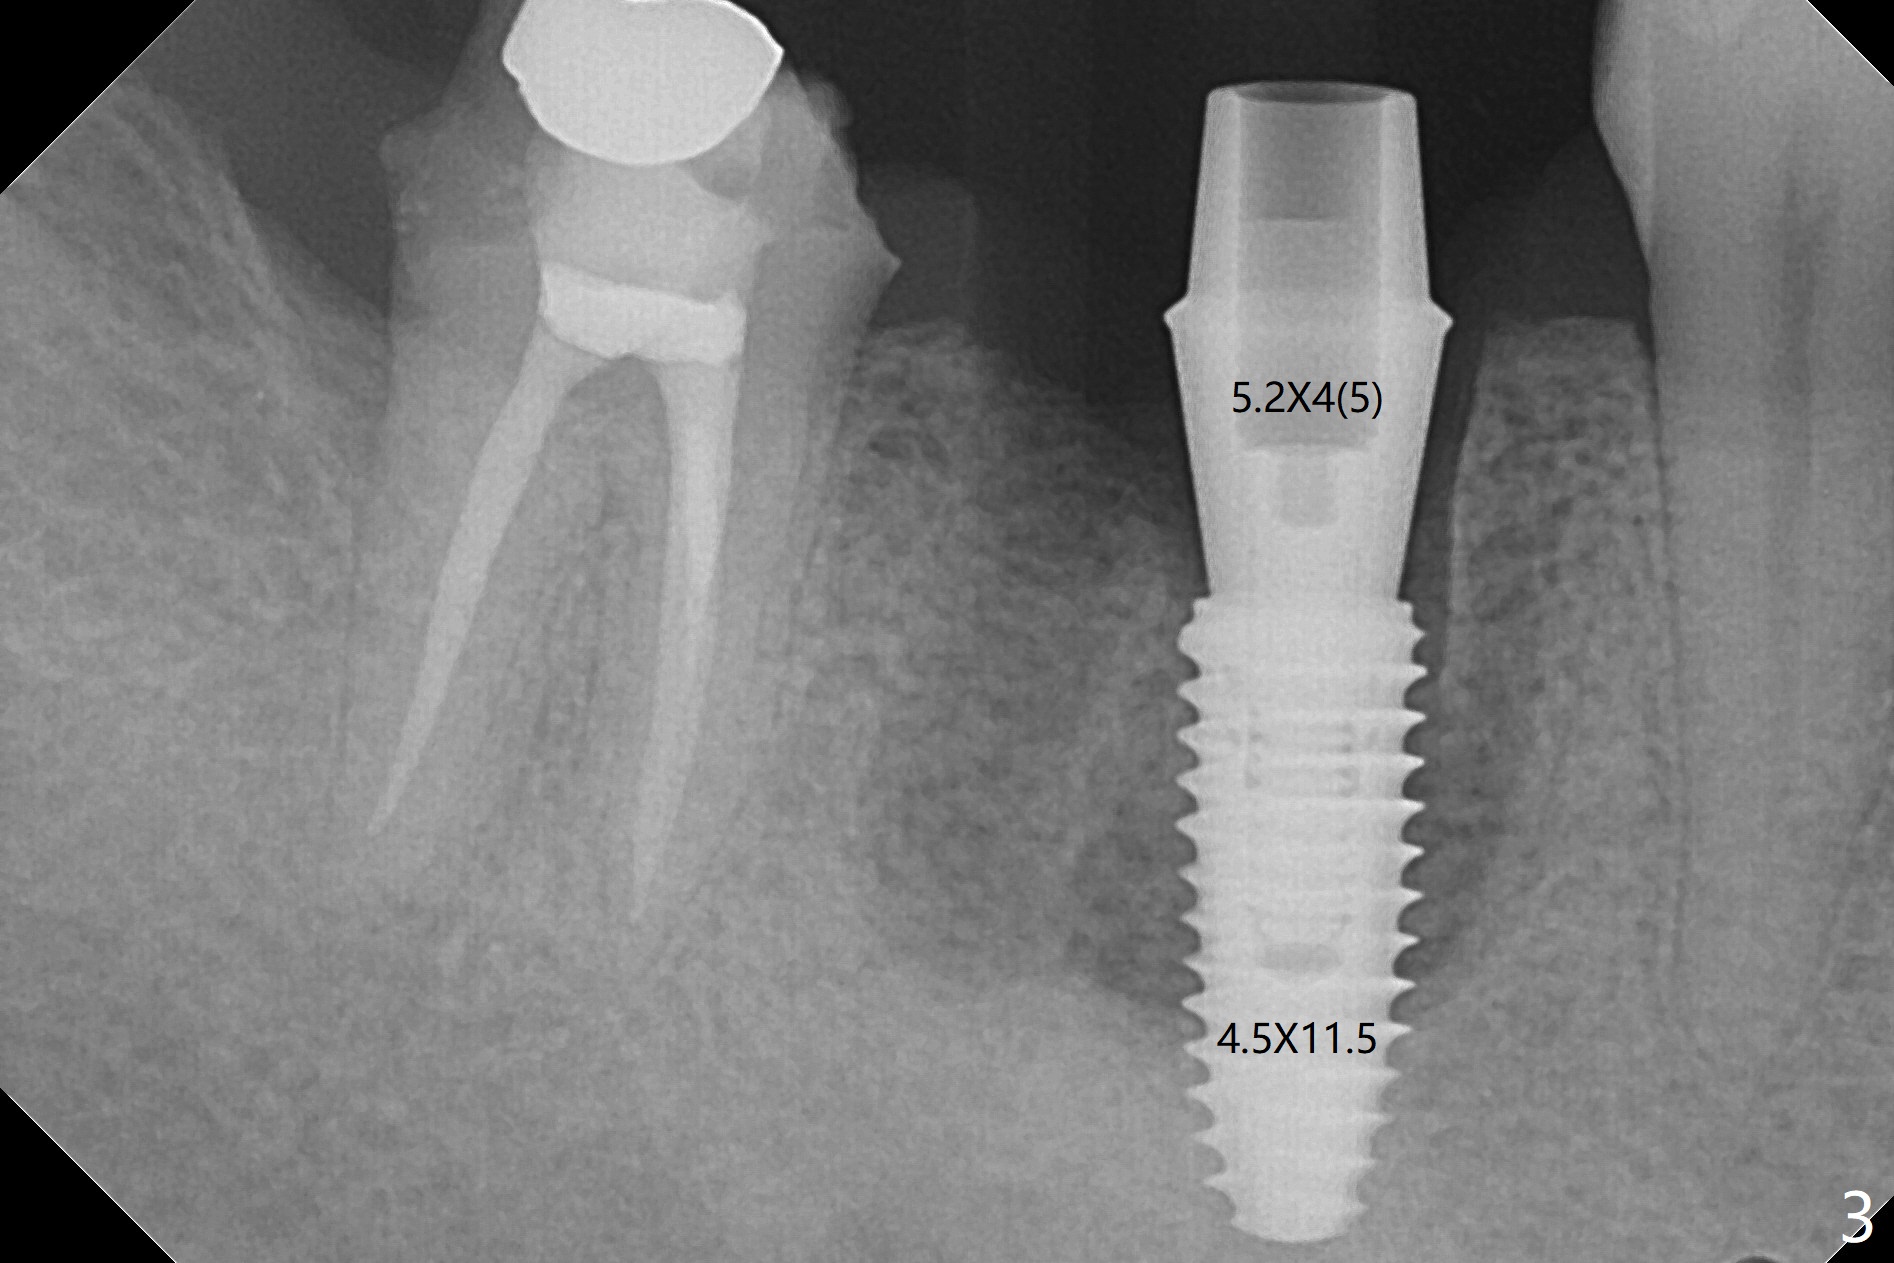

When the tooth #30 is extracted, the gingiva buccal to the septum (S in Fig.1,2 (P: papilla between the mesial and distal roots)) collapses. The latter is fixed with placement of a 4.5x11.5 mm implant (with guide), a 5.2x4(5) mm cemented abutment (Fig.3) and mixture of cortical bone (125μm – 850μm) and cortical/cancellous bone (.5-1 mm) with PRF (sticky bone, B in Fig.4-6). After placement of 2 pieces of PRF membrane over the bone graft, a temporary crown is fabricated to cover the buccal defect (Fig.7 T). Approximately 7.5 mm of the buccal threads are covered by the thick layer of bone graft (Fig.8 B). It is amazing to expect that the bone graft will turn into the buccal plate. It would be better if a narrower implant (4 instead of 4.5 mm) were placed more lingually or there were < 4 mm implant thread exposure (Fig.9). The gingiva reacts to the provisional nicely 7 days postop (Fig.10). The provisional will be removed for modification in 1 month. The patient complains of bad smell from the provisional 2 weeks postop. The provisional is removed. The distal socket (Fig.11 D) is healing, whereas the buccal bone graft (Fig.12 B) seems not have been vascularized. Pedicled flaps (I) should be transferred to cover the buccal bone graft. The margin of the provisional is polished, becomes short, and covered by periodontal dressing, which dislodges 2 days later. One week later, granulation tissue is forming apically with use of oral antibiotic and water jet (Fig.13 *). The bad smell reduces. The superficial loose bone graft changes colar and becomes detached 1 month 10 days postop. The temporary crown with the shortened buccal shelf is reseated for self cleansing or reapplication of PRF if needed (Fig.14).